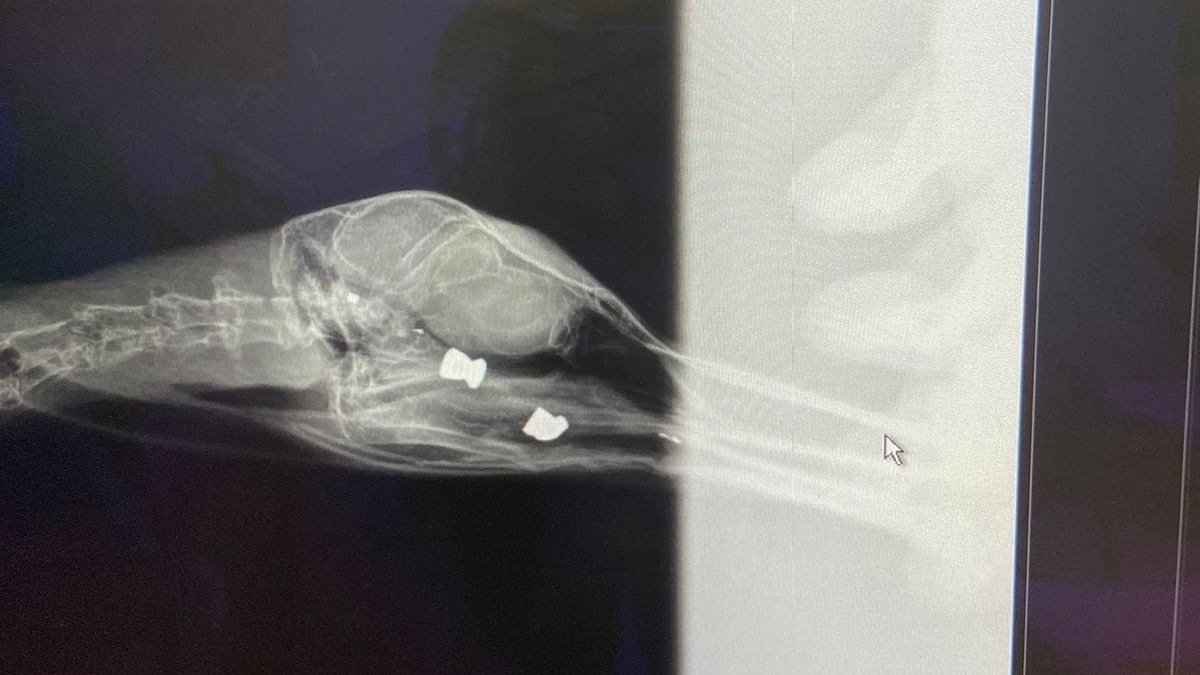

В Красносельском районе Петербурга на улице Котина, 7, нашли и подобрали чайку, которая не могла улететь, сообщили в группе Красносельского и Кировского районов Петербурга «ВКонтакте». Птицу отнесли к ветеринару.

«На приеме у врача пришли в шок: рентген показал шесть пуль от травматического оружия в теле птицы. Три из них в голове», — написал автор поста.

В комментариях под постом пользователи сети обращают внимание на то, что пули, которые видны на рентгене в крыле у птицы, вероятнее всего, от пневматического, а не травматического оружия.